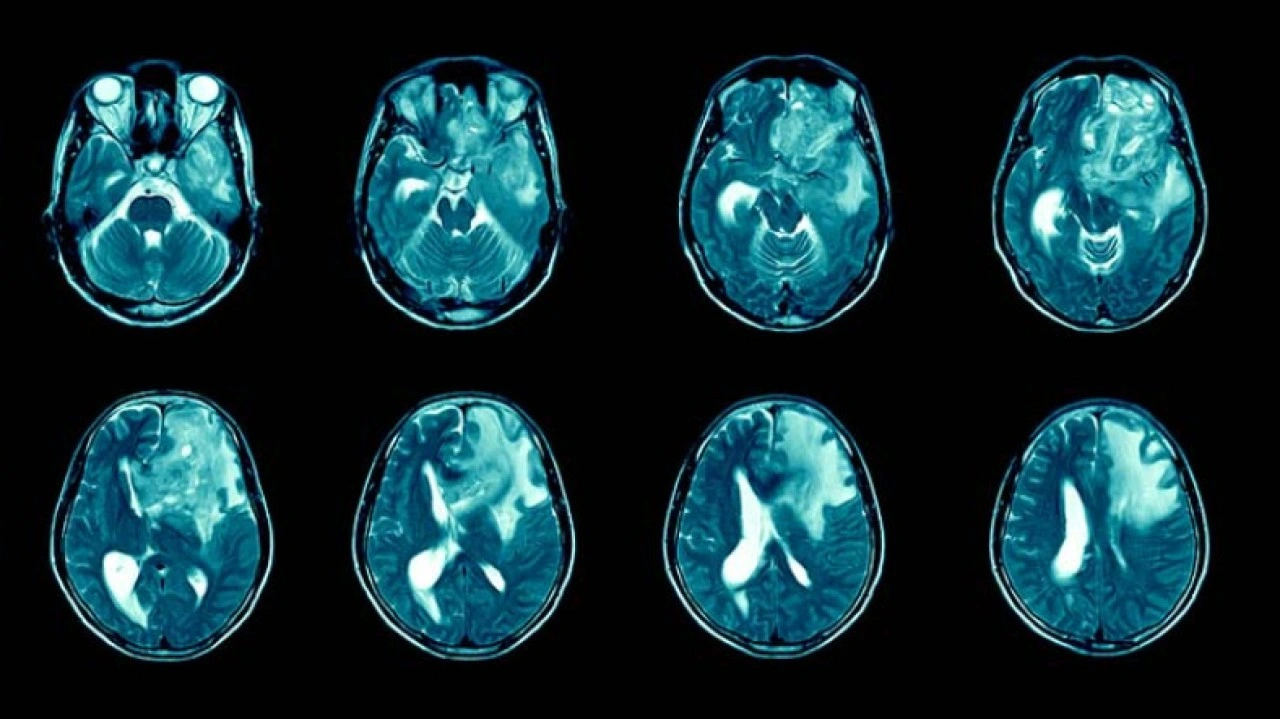

Glioblastoma, beyin kanseri türleri arasında en ölümcül türlerden biri olarak biliniyor. Bu hastalık ortaya çıktıktan sonra hastaların büyük kısmı 1-1,5 yıllık bir süreçte hayatını kaybediyor ve 5 yıldan uzun süre hayatta kalanların oranının ise sadece %7 olduğu belirtiliyor. Üstelik bu süreç boyunca hastalık baş ağrısı, hafıza kaybı, düşünme ve davranış değişiklikleri gibi belirtilere de sahip.

Şu anda kullanılan tedaviler arasında ameliyat, radyasyon ve kemoterapi yer alıyor. Bu yöntemler geçici çözümler sunuyor ve hastalığın kendisini değil semptomlarını tedavi ediyor. Vücut bu kanser hücrelerine karşı doğal bir savunma geliştiremiyor ve verilen ilaçlar da, kan beyin bariyerini genellikle aşamıyor.